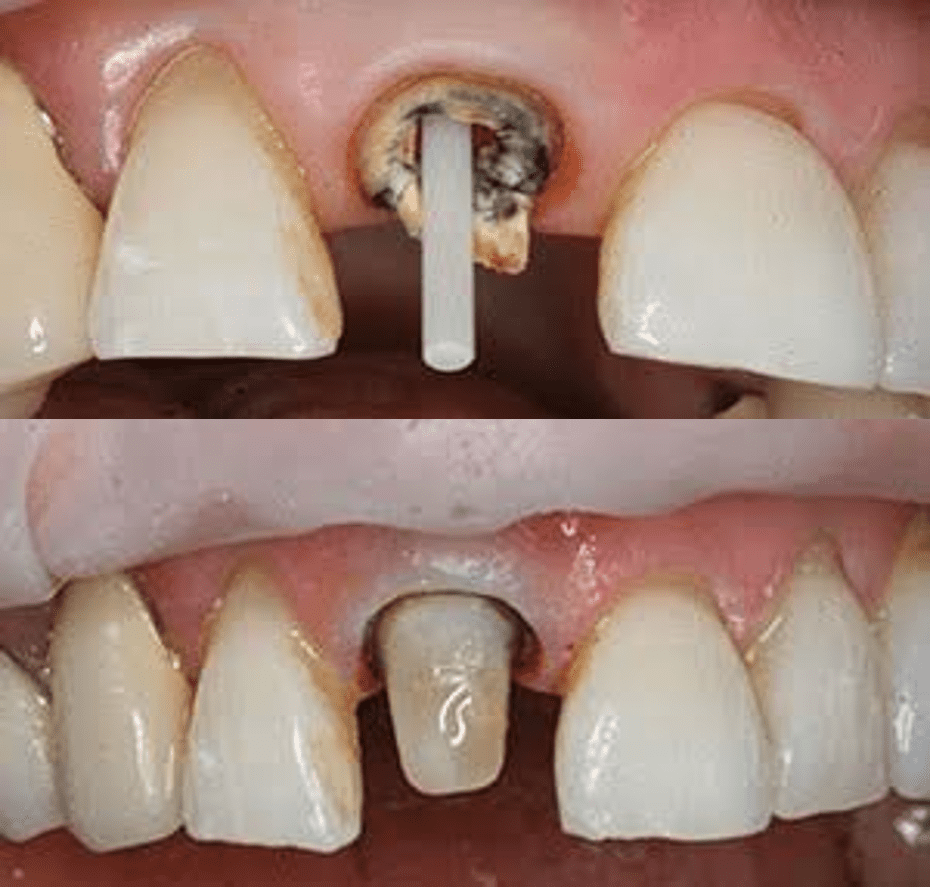

Conservative Dentistry and Endodontics is the branch of dentistry which deals with the treatment of caries , malformed, discolored , unesthetic, or fractured teeth, pulpal and periapical diseases and dental pain management. Our vision is to create an environment conductive for enhancement of restorative and endodontic skills.The department has set up its own high standard in patient care, education and research.

• More than 1000 Root Canal Treatments by each Post Graduate Student under Rubber Dam Isolation.

• Retreatment Procedures

• Fibre Post –Core

• Perforation Repairs